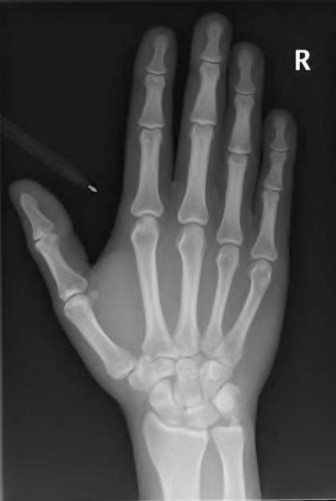

A 35-year-old woman reports wrist pain after a fall onto an outstretched hand. On exam, she has focal tenderness over the wrist snuffbox. A radiograph and CT image are shown in Figures A and B. What is the proper treatment of her injury?